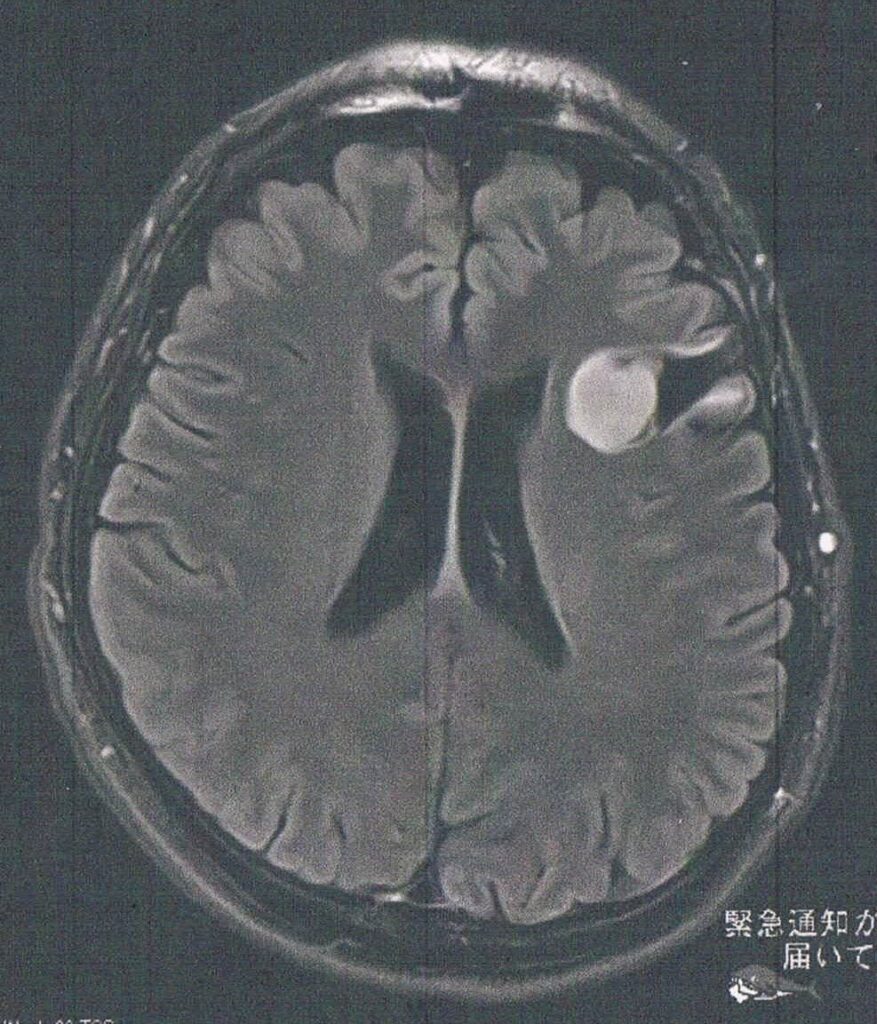

- びまん性星細胞腫グレード2(悪性転化しやすい腫瘍)

- 前回のMRIと変化は無いように見えるが、数年単位では大きくなっている

- てんかんなどの症状が無く様子見を継続

- 大きくなってもまだ取ることは可能と思うとのこと